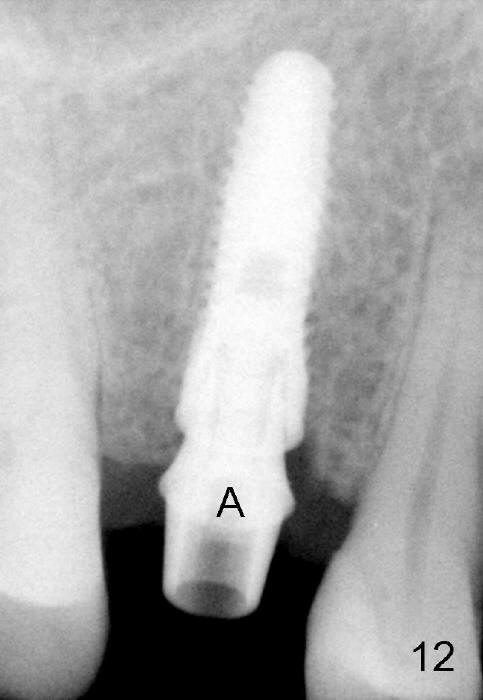

Due to insurance termination, restoration has to be done 2 months post implantation. Both the soft (Fig.10 *) and hard (Fig.11) tissues heal normally. A cemented abutment is placed (Fig.12 A). Fig.13 is taken 5 months post cementation. There is no bone resorption.